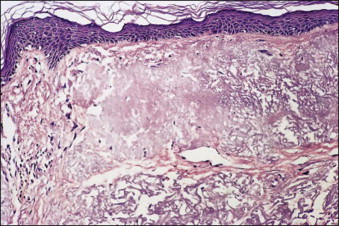

In addition to collagen, elastic fibers also undergo significant alterations with age. Elastin makes up about 4% of the skin’s dry weight. It is characterized by its elastic extensibility – the ability to stretch under stress but also to recoil and return to its original shape after the stress is removed. Therefore elastin and elastic fibers are inherently important in skin elasticity. It is estimated that as early as young adulthood, elastic fibers diminish in size and number. By late adulthood elastin is degraded, and elastic fibers lose their structural integrity leading to diffuse fragmentation, especially at the DEJ – a condition known as solar elastosis ( Fig. 1.2 ). Furthermore, elastic fibers display more cross-linking, progressive calcification, and at times trans-epidermal extrusion from the dermis ( Fig. 1.3 ). In addition to these structural changes, elastic fibers also endure compositional changes, exhibiting decreases in essential components including elastin and fibrillin. Fibrillin remains abundant in the deeper zones of the dermis; however, it becomes significantly reduced in the upper zone of the dermis. Aged skin displays significant decreases in fibulin-5, an extracellular protein that provides a support base for elastic fibers. Studies have shown that a decrease in fibulin-5 expression may be one of the earliest changes, and therefore markers, of cutaneous aging.